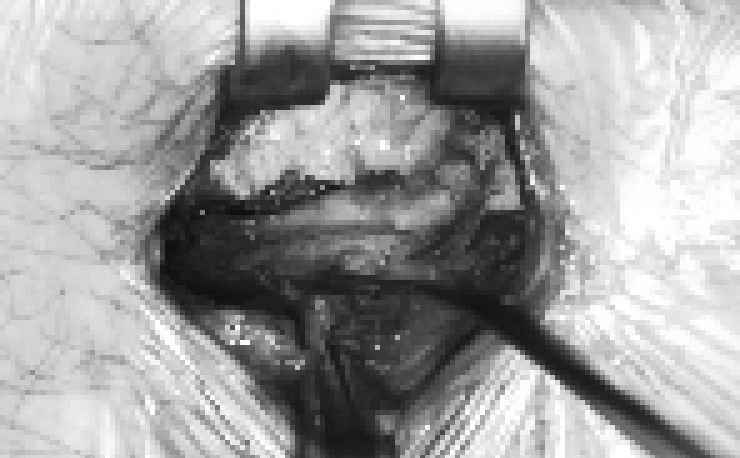

디스크 절제를 위해서는 이렇게 피하, 근육층, 그리고 추체의 궁부분까지

어쩔 수 없이 절제를 해야하는데요.

이것이 추후 재탈출의 영향을 줄 수 있기 때문에

이 과정에서 상처들이 잘 아물때까지는 제대로된 재활이 굉장히 중요하다는 것입니다.